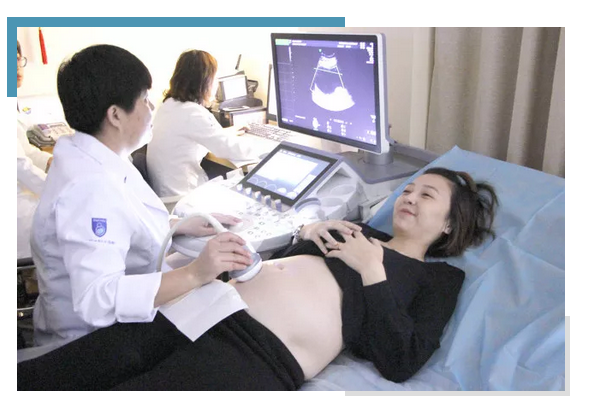

超声检查时,首先对胎儿进行头臀长(CRL)及双顶径测量确定超声孕周,然后顺序检查胎儿结构,观察一些重要的指标如胎心、胎动、脐带与胎儿链接部位、胎儿四肢发育、颅内脉络丛等,以除外胎儿异常如前脑无裂畸形、脉络丛囊肿、脐疝及其它发育异常。

颈部透明带厚度于胎儿长轴矢状切面进行测量,测量时胎头与脊柱呈一直线。放大倍数调节至胎儿躯体占屏幕大小的3/4左右。

NT值是超声中测量妊娠10-14周胎儿颈项透明层厚度,凡测值<2.5mm时判断为正常,凡测值大于或等于2.5mm时,诊断为颈项透明层增厚。当发生极度增厚时,可形成胎儿颈部水囊瘤,这种胎儿是属于先天性疾病。

、由于孕11周前胎儿过小无法难以观察颈后透明带,而孕14周后由于胎儿逐渐发育,可能会将颈项透明层出多余的体液吸收,影响检测结果,因此孕妇最好在怀孕11-14周内去做NT,以免检查结果不准确。

B超检查既能对胎盘定位、羊水测量,又能对单胎多胎、胎儿发育情况及有否畸形和葡萄胎等作出早期诊断。

孕期B超很重要,孕早期的B超检查是确诊怀孕的重要依据,检查是否宫外孕,孕囊大小,胎芽大小等胎儿发育情况,有无胎心搏动及卵黄囊等。孕中期的B超检查,可以面部、神经系统、消化系统、泌尿系统等有无畸形。